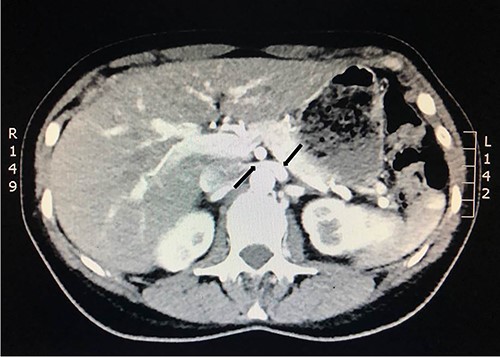

She underwent a flexible ureterorenoscopy 2 months later which further demonstrated no cause for hematuria within the collecting system. An ECHO cardiography was performed to out rule an embolic event to the kidney due to the patchy perfusion noted and was normal. A repeat CT angiogram showed resolution of the congestion of the left kidney, but a narrow LRV as before (Fig. 8).

Computed tomography angiogram 6 months later showing pre-compressed LRV (right arrow); and compressed LRV (left arrow), but resolution of the congestion and swelling of the left kidney.